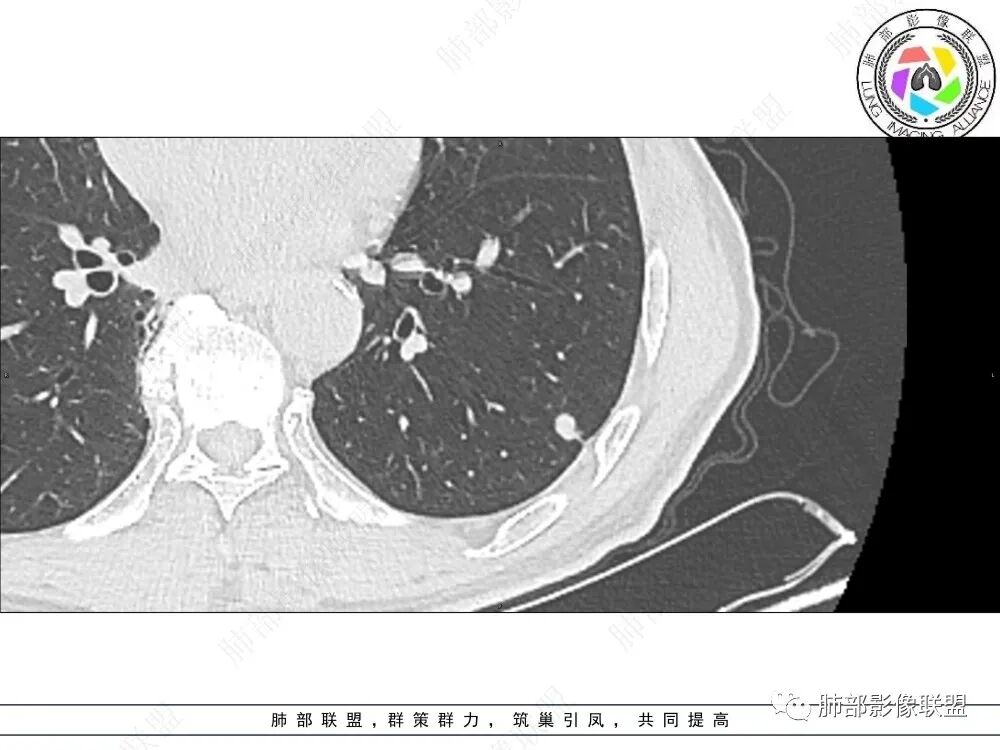

2、影像特点:左肺上叶尖后段病灶结合病史考虑消融术后改变,双肺下叶胸膜下可见多发大小不等的实性结节,周围似乎有晕,边缘平直为主,未见深分叶,部分可见邻近胸膜牵拉,张力不高,增强后呈轻中度强化。

3、总结:中老年男性,间断胸痛就诊,余无明显其他临床体征。既往肺癌病史,定期复查,一年左右双肺新发多发结节,常规需要鉴别炎性肉芽肿和肺癌转移。病灶以胸膜下为主,边界清楚,尽管转移是可以的,但混合磨玻璃时期腺癌相对惰性,短期内难以出现如此转移灶。况邻近胸膜牵拉,这在转移中也相对要少见。病灶多发,但没有新旧不等,没有树芽,病灶及时间线不支持继发性肺结核。病灶散在,胸膜下为主,周围可见少许晕征,部分病灶边缘比较平直,影像上较为符合隐球菌等肉芽肿性炎。

病史时间:2018年8月12日确诊左肺上叶肺腺ca射频消融,2020年1月13日左肺下叶未见结节,2021年3月14日新发双肺下叶(视频图)见4枚实性小结节,边清,目测低强化,胸膜下的结节(3个)与胸膜粘连的特点,无收缩力,前后1年余倍增明显结节,多发,支持炎性肉芽肿结节,隐球菌荚膜抗原检查,其次与转移鉴别,非随机,位置仅双肺下叶,可能性小,建议左肺下叶后基底结节定位穿刺活检!